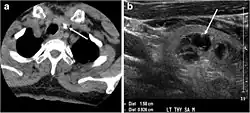

Fig. 4. A 45-year-old male patient presented with anterior mediastinal metastatic PTC lesions and occult primary on imaging. Histopathology examination of the resected thyroid gland revealed micro-foci of PTC; the largest, in the isthmus, measured 4 mm. a transverse greyscale ultrasound of the thyroid demonstrates homogeneous gland with normal echogenicity and size. No focal lesion or micro-calcifications. b Non-enhanced CT scan obtained as part of PET/CT examination shows a heterogeneous, large, relatively dense anterior mediastinal mass (white arrow) with peripheral calcification (arrowheads). Thyroid gland has normal CT appearance with no abnormal FDG uptake (not shown).[1] -